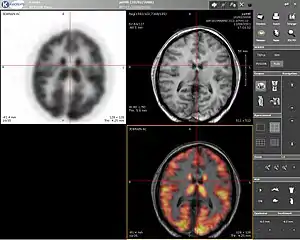

Positron emission tomography

Positron emission tomography (PET) is a nuclear medicine imaging technique which produces a three-dimensional image or picture of functional processes in the body. The theory behind PET is simple enough. First a molecule is tagged with a positron emitting isotope. These positrons annihilate with nearby electrons, emitting two 511 keV photons, directed 180 degrees apart in opposite directions. These photons are then detected by the scanner, which can estimate the density of positron annihilations in a specific area. When enough interactions and annihilations have occurred, the density of the original molecule may be measured in that area. Typical isotopes include 11

C, 13

N, 15

O, 18

F, 64

Cu, 62

Cu, 124

I, 76

Br, 82

Rb, 89

Zr and 68

Ga, with 18

F being the most clinically utilized. One of the major disadvantages of PET is that most of the probes must be made with a cyclotron. Most of these probes also have a half life measured in hours, forcing the cyclotron to be on site. These factors can make PET prohibitively expensive. PET imaging does have many advantages though. First and foremost is its sensitivity: a typical PET scanner can detect between 10−11 mol/L to 10−12 mol/L concentrations.